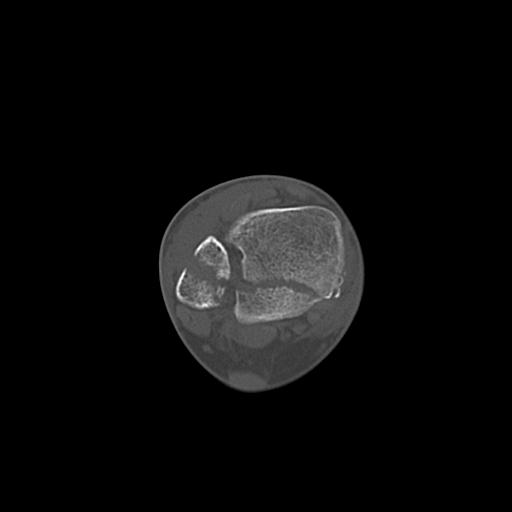

49554 3/13 膝 4R 3/16 4R 1/18 2R 78歳男性 膝蓋骨骨折